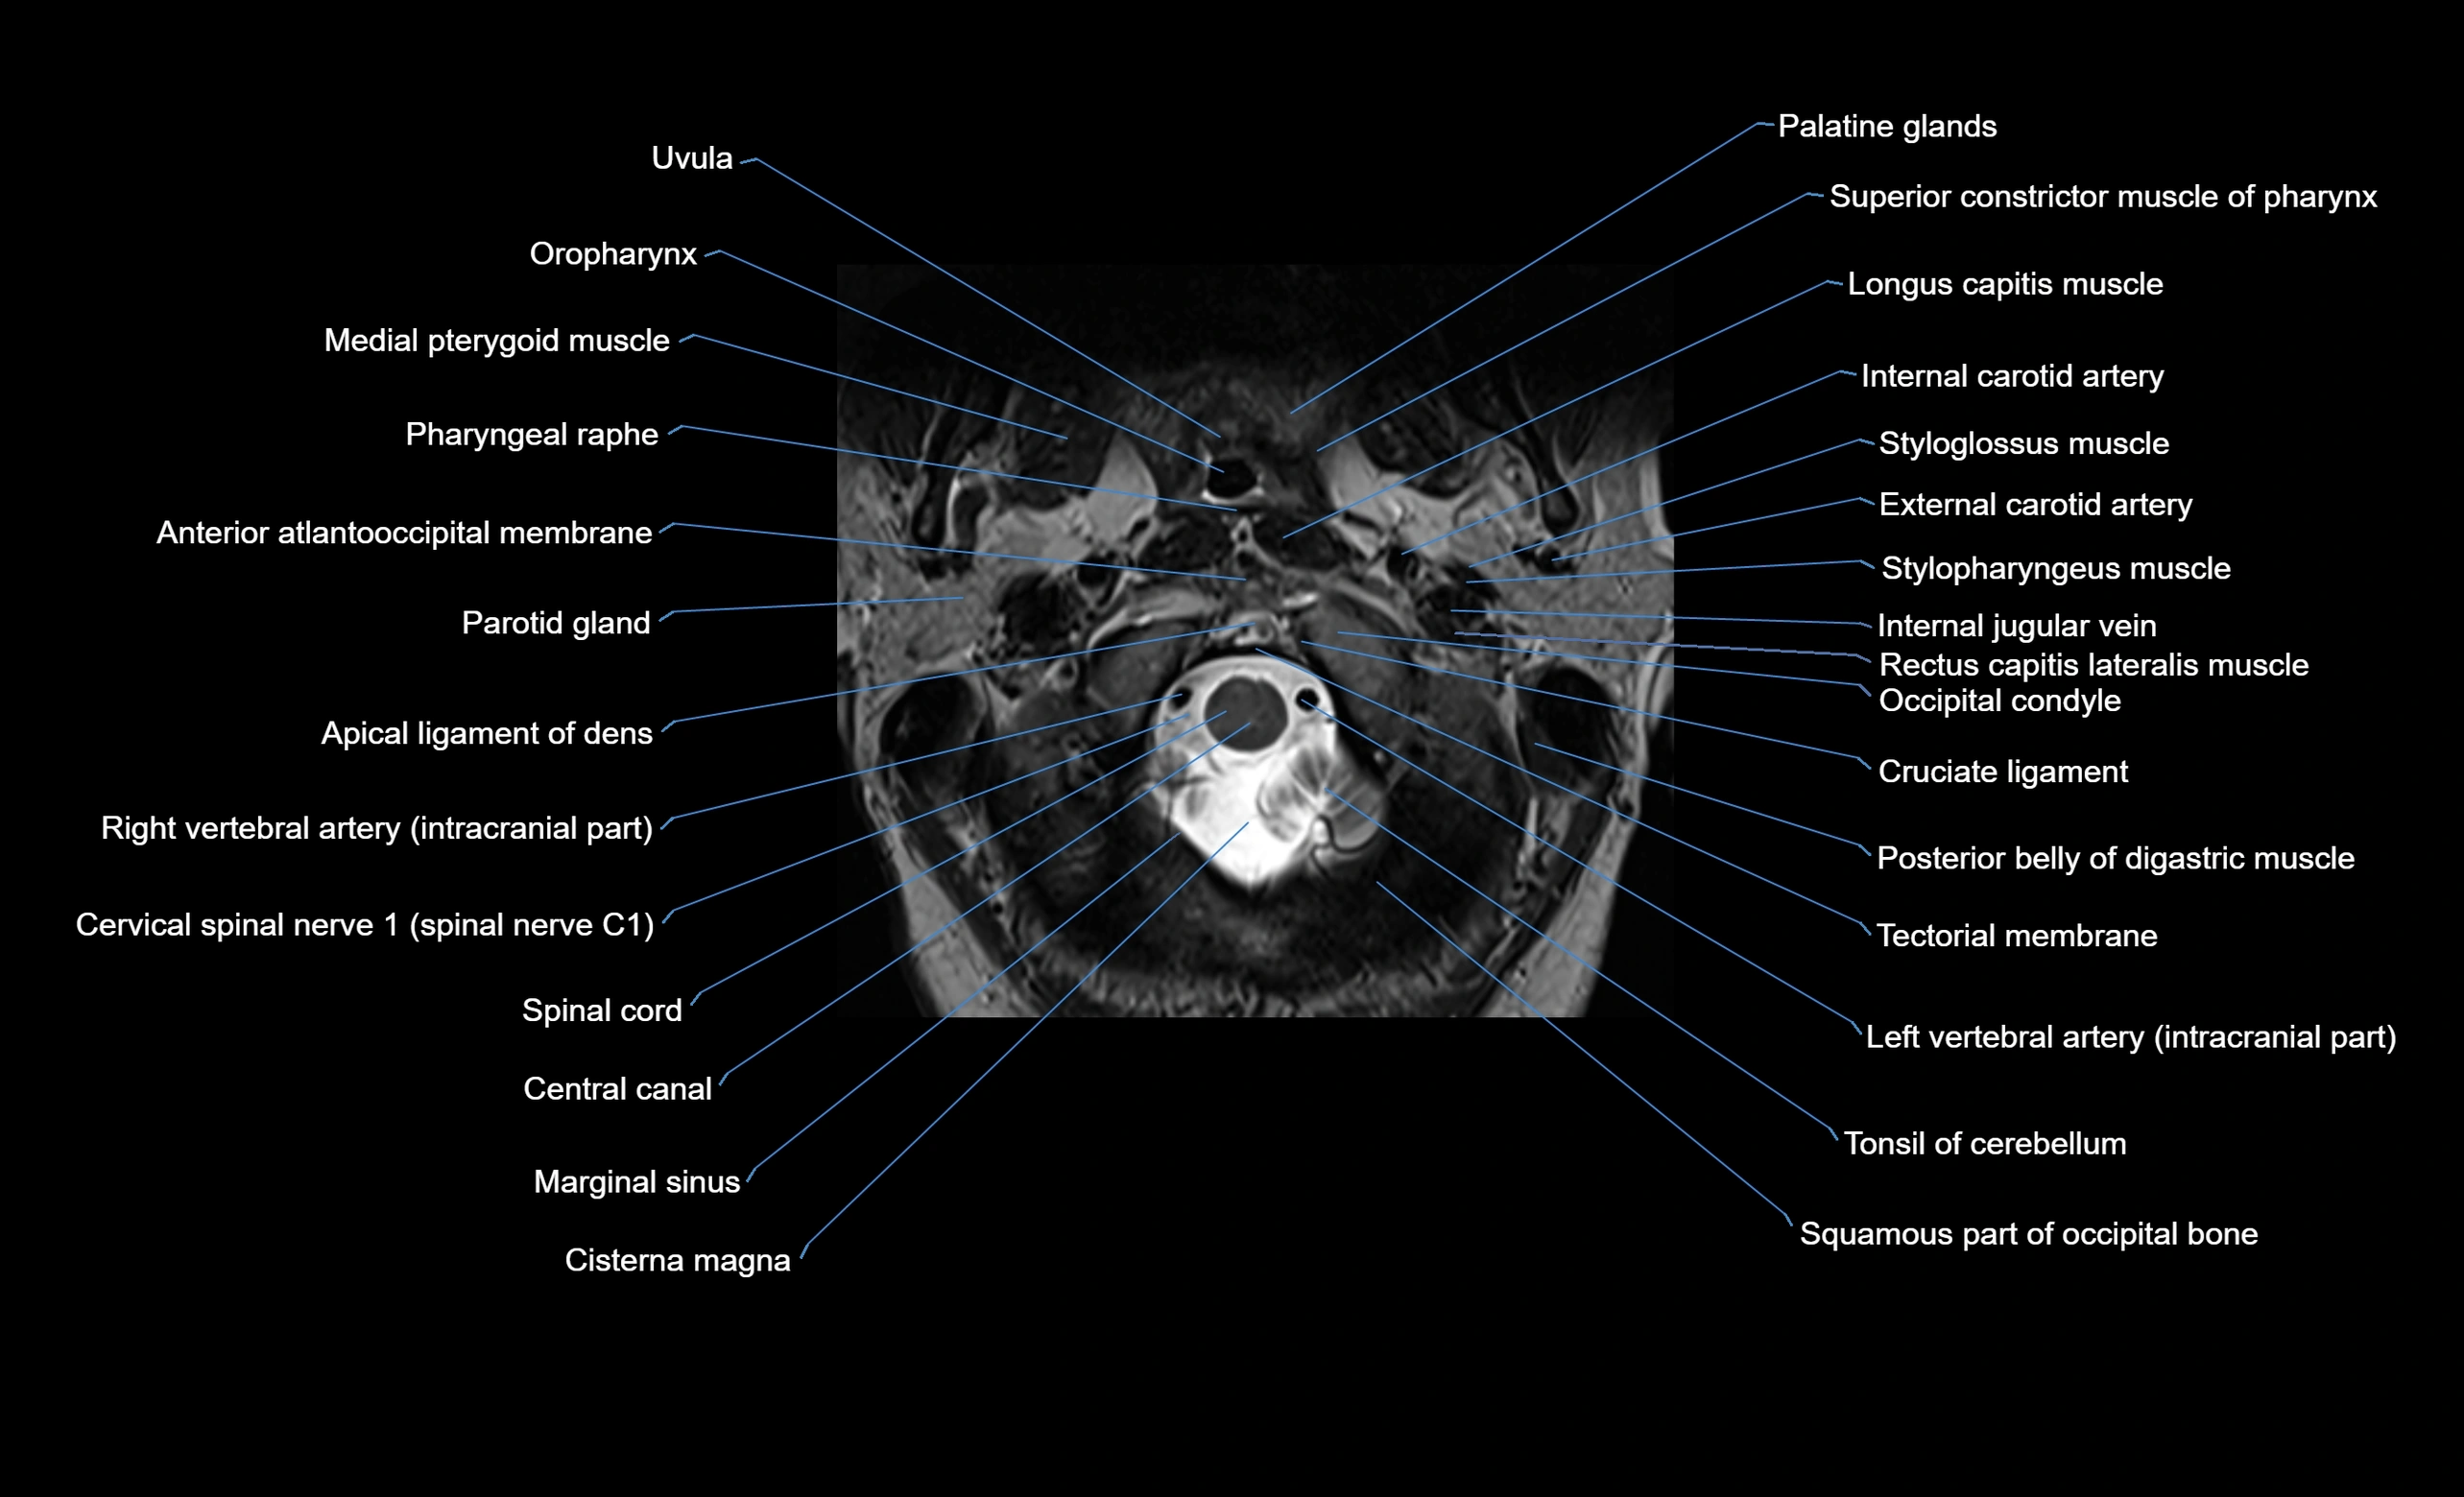

MRI image

image